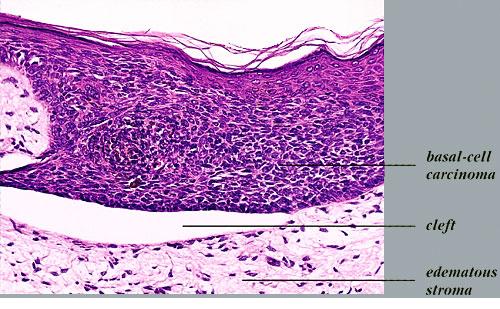

Bacillary angiomatosis = الورام الوعائي العصوي BACILLARY ANGIOMATOSIS Epidemiology BA is most commonly seen in patients with acquired immunodeficiency syndrome (AIDS) and a CD4 count less than 50 cells/mm3, with an incidence of 1.2 cases per 1000 at-risk patients Patients with other forms of immunosuppression, including patients with leukemia and recipients of organ […]